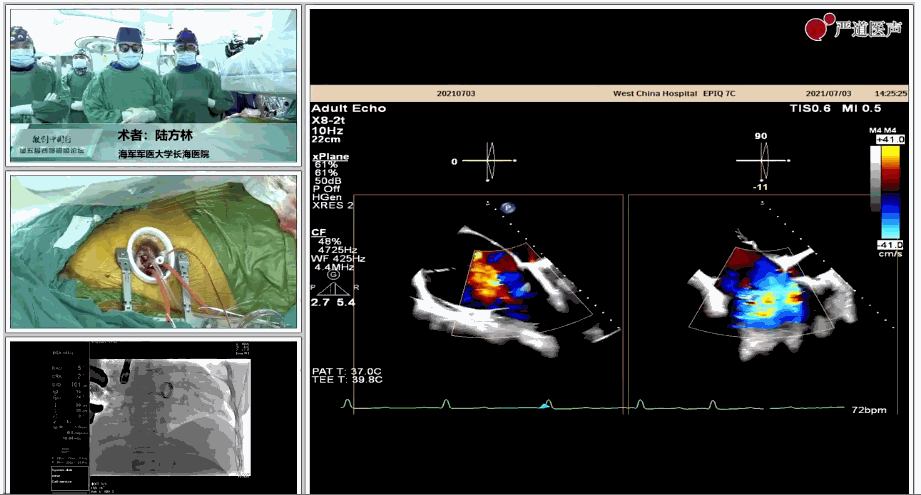

7月3日下午,海軍軍醫(yī)大學附屬上海長海醫(yī)院心血管外科徐志云、陸方林團隊在論壇中分享了經(jīng)導管三尖瓣置換術(shù)(LuX-Valve®)的手術(shù)直播演示。線下會議由陶涼教授、潘文志教授、喬晨暉教授共同參與討論和臨床分享。

陸方林教授分享的是一例極重度三尖瓣返流的患者采用健世科技(LuX-Valve®)經(jīng)導管三尖瓣置換系統(tǒng)進行的手術(shù)直播演示。此例患者為69歲女性,入院前17年行二尖瓣機械瓣置換術(shù),術(shù)后長期服用華法林抗凝,既往“2型糖尿病”病史5年,“雙下肢水腫”3年。3個月前患者出現(xiàn)腹脹、雙下肢水腫,伴活動后暈厥,伴黃疽、皮膚濕癢、牙齦出血,癥狀持續(xù)加重,遂入院治療。入院后行心臟CT、心臟超聲檢查,提示:“三尖瓣關(guān)閉不全(極重度),二尖瓣置換術(shù)后,心功能III級”。徐志云、陸方林微創(chuàng)三尖瓣置換團隊對該患者的病情進行了充分的評估和討論。由于患者有開胸二尖瓣置換手術(shù)史,且病史時間長,同時存在相關(guān)合并癥,傳統(tǒng)外科手術(shù)風險極高(STS評分:8.315%),最終決定采用三尖瓣LuX-Valve®瓣膜系統(tǒng)對患者進行治療。

▲術(shù)中食道超聲顯示三尖瓣極重度返流